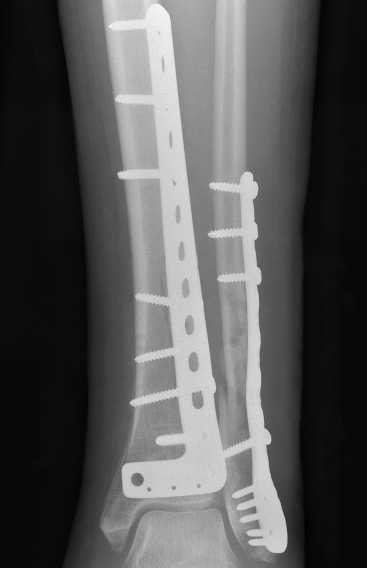

ORIF with Plates

Principle

Restore articular surface

Fix articular surface to metaphysis

Anatomical Plates

Synthes medial plate Synthes anterolateral plate

Attach metaphysis to diaphysis

- anatomically contoured low profile locking plates

- anterolateral L shaped plate via anterior wound

- small incisions proximally to insert screws

- 8 cortices above fracture

- small medial incision to insert medial plate percutaneously / MIPO techniques